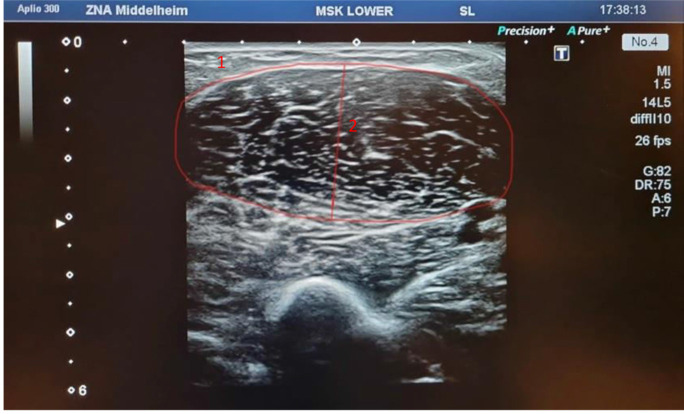

Objectives: To assess the link between ultrasonographic measurements of the biceps brachii and total muscle mass measured by bio-impedancemetry in hospitalized older patients.

Methods: A prospective observational study was conducted. The study included patients older than 65 years admitted in internal medicine, acute geriatrics, orthogeriatrics and rehabilitation departments. All measurements, ultrasonographic measurements and muscle mass and function by bio-impedancemetry and dynamometry, were taken within the first 48 hours of admission.

Results: In total 19 patients were included, the mean age was 85.4 ± 3.9 years and 7 (36.8%) were females. Very strong direct correlations were obtained in the entire cohort in both biceps brachii cross-sectional area and muscle thickness with skeletal muscle mass displayed in kilograms.

Conclusion: Biceps brachii looks like a very good muscle measuring tool: easy, comfortable, fast, good correlated with total body muscle mass. This muscle could effectively be used for the assessment of muscle mass in the diagnosis of sarcopenia since it reflects muscle mass precisely, however more studies are needed to provide reference values in all age cohorts.